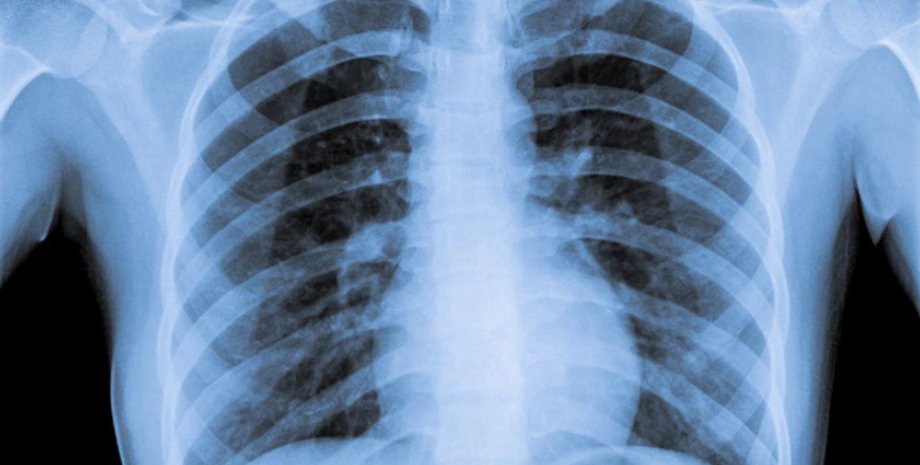

Всемирная организация здравоохранения предупредила, что, поскольку курение ухудшает функцию легких, существует повышенный риск серьезных симптомов, если курильщики заражаются респираторными инфекциями, включая коронавирусы. Covid-19 — инфекционное заболевание, поражающее в первую очередь легкие.